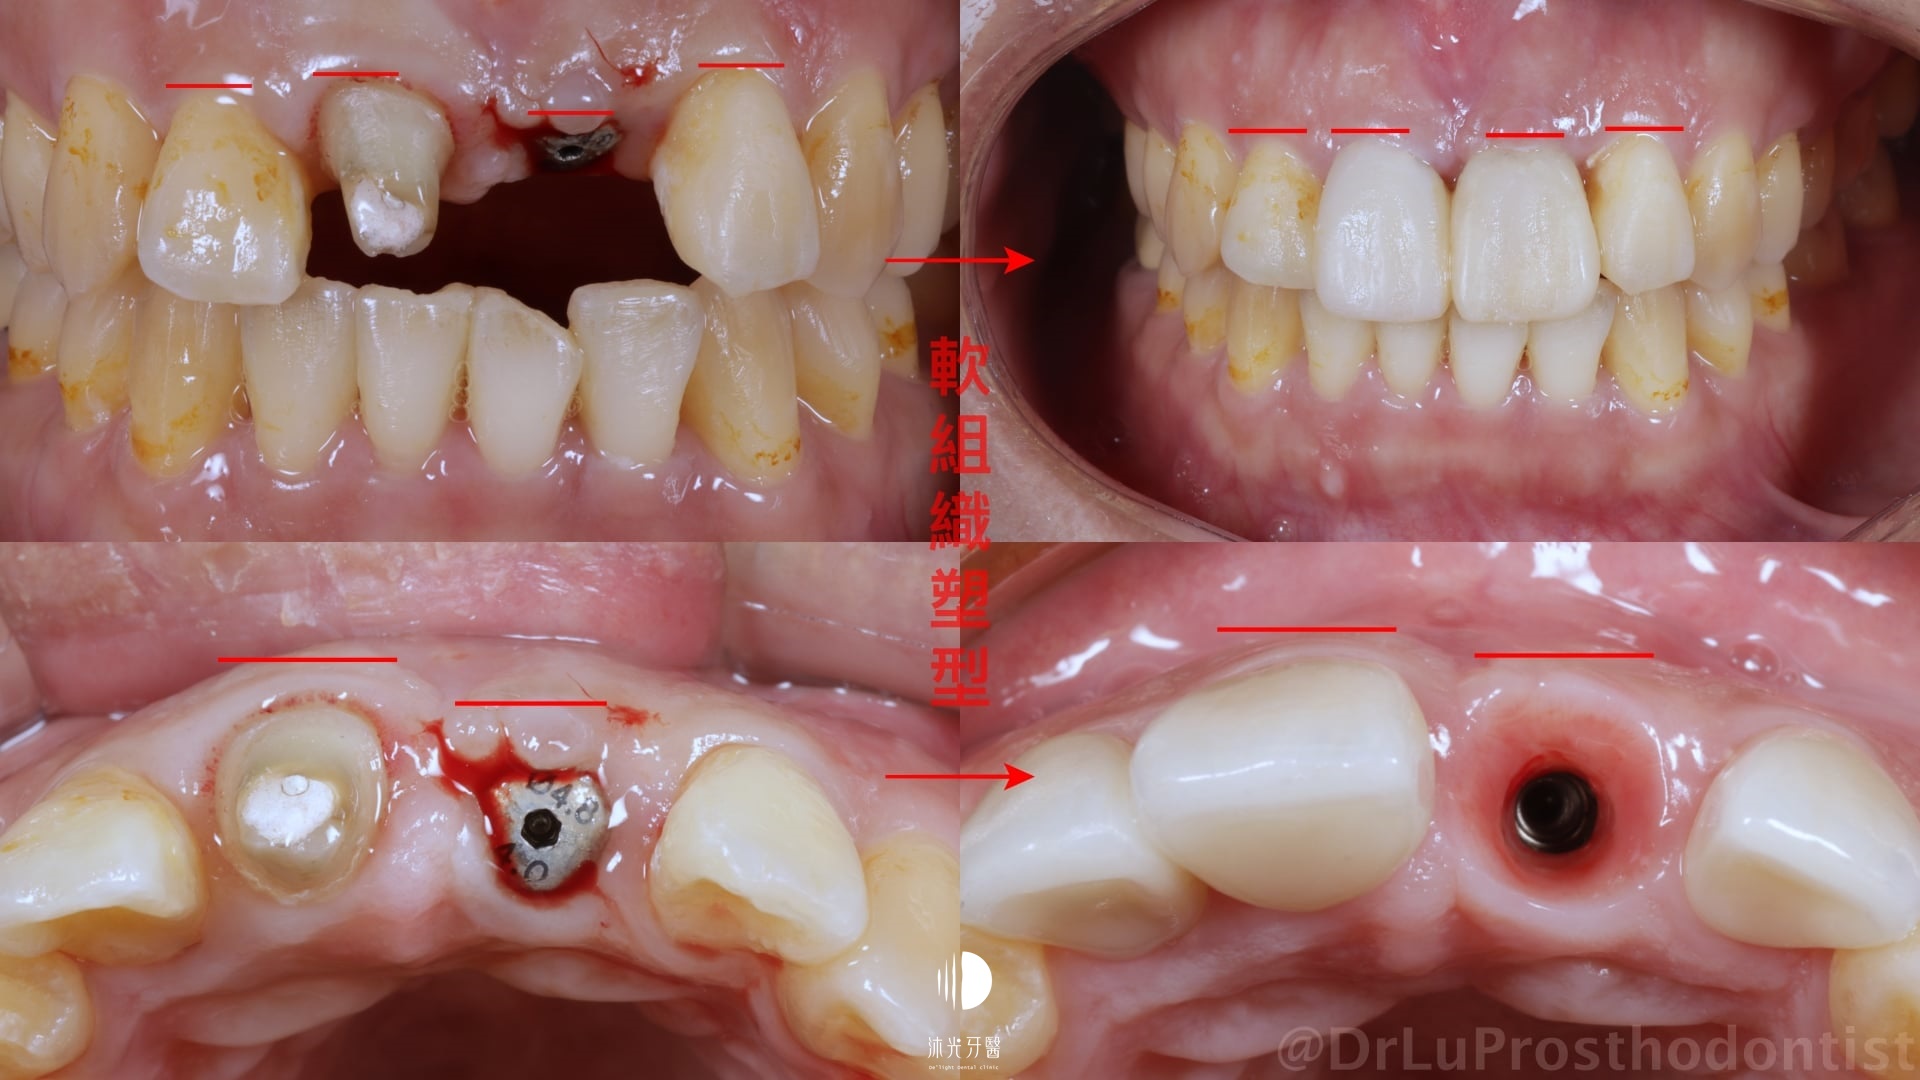

矯正治療完成後才安排縱裂的左側門牙拔牙、補骨、植牙等流程;可以看到即使門牙植牙區水平方向的組織量不足,但在條件良好的情況下單單透過植牙臨時假牙的形態去塑型周圍牙肉,還是可以達到正面觀時不錯的結果,達到患者希望減少手術次數的要求。

一些創傷伴隨嚴重齒槽骨損傷的患者就沒有這麼簡單了,可能會需要大範圍的補骨及軟組織手術或是合併假牙肉的贋復物才有機會找回自然好看的笑容,之後的篇幅再和大家分享囉~~大家出門在外務必注意交通安全!